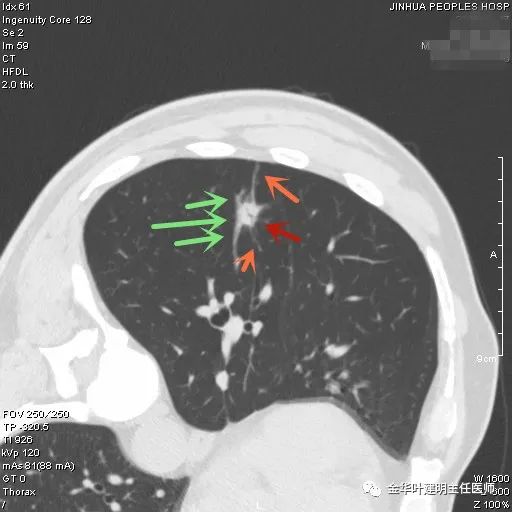

上图示结核。我们发现其有明显的卫星灶,如绿色箭头所示,主病灶处也是周边有模糊区域,病灶整体密度较为均匀(肿瘤容易生长不均致密度欠均匀,显杂乱)。